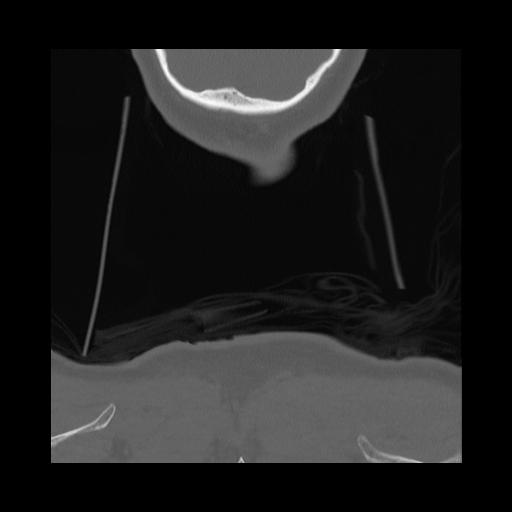

16 HUESO,,Coronal,2.000,HUESO,Coronal,